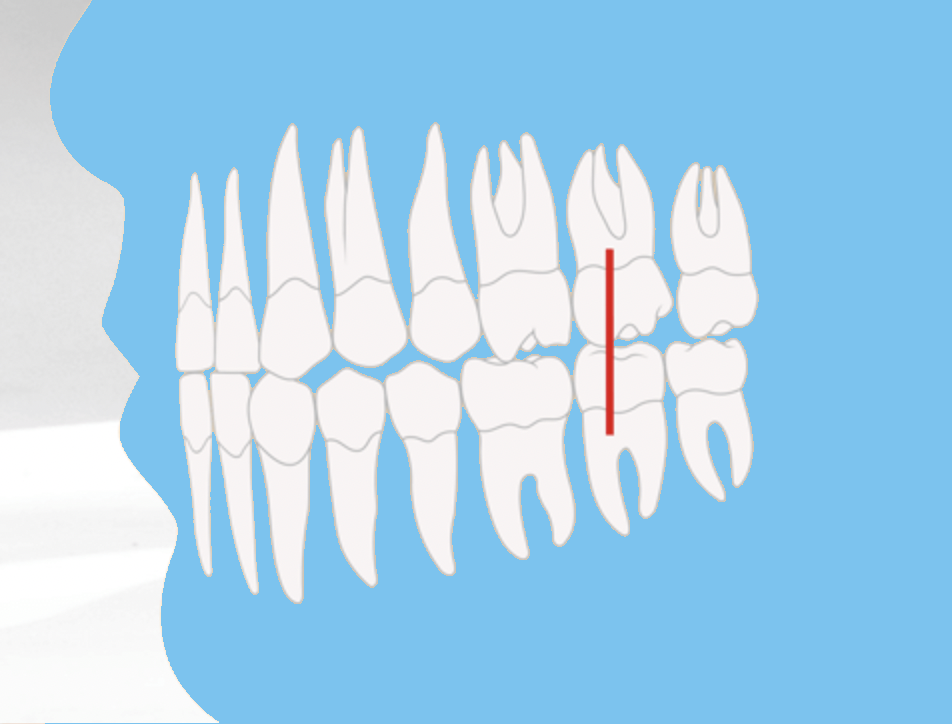

Das Ordnungssystem der Zahn- und Kieferfehlstellungen: Die Angle-Klassen

Die Angle-Klassen sind ein international anerkanntes Ordnungssystem, um Zahn- und Kieferfehlstellungen systematisch zu diagnostizieren und zu bewerten. Grundlage ist die Lagebeziehung der ersten bleibenden großen Backenzähne – der sogenannten 6-Jahr-Molaren – von Ober- und Unterkiefer zueinander. Entwickelt wurde das Klassifikationssystem bereits Anfang des 20. Jahrhunderts von dem amerikanischen Kieferorthopäden Edward H. Angle. Trotz zahlreicher moderner Diagnosetechniken ist es bis heute ein fester Bestandteil der kieferorthopädischen Beurteilung.

Angle-Klasse I: Der Neutralbiss

Die Angle-Klasse 1 beschreibt ein reguläres, gesundes Gebiss ohne Abweichungen in der Bisslage. Man spricht auch von einem Neutralbiss. Hierbei trifft der vordere Höcker des ersten großen Backenzahns im Oberkiefer genau in die Lücke zwischen den beiden Höckern des gegenüberliegenden ersten großen Backenzahns im Unterkiefer.

In dieser Stellung beißen die Zähne von Ober- und Unterkiefer harmonisch aufeinander, wodurch sowohl die Kaufunktion als auch die Ästhetik optimal sind. Auch das Gesichtsprofil wirkt ausgeglichen, da keine Abweichungen in der Kieferlage vorliegen.

- Angle-Klasse I (Neutralbiss): normale Verzahnung, leichte Abweichungen möglich.

Angle-Klasse I: Grundlage für die Einteilung von Zahnfehlstellungen in der modernen Kieferorthopädie

Infografik: Die Angle-Klassen (I - III)

Angle-Klasse I

Neutralbiss - reguläres Gebiss Ober- & Unterkiefer im Gleichgewicht Gesichtsprofil harmonisch